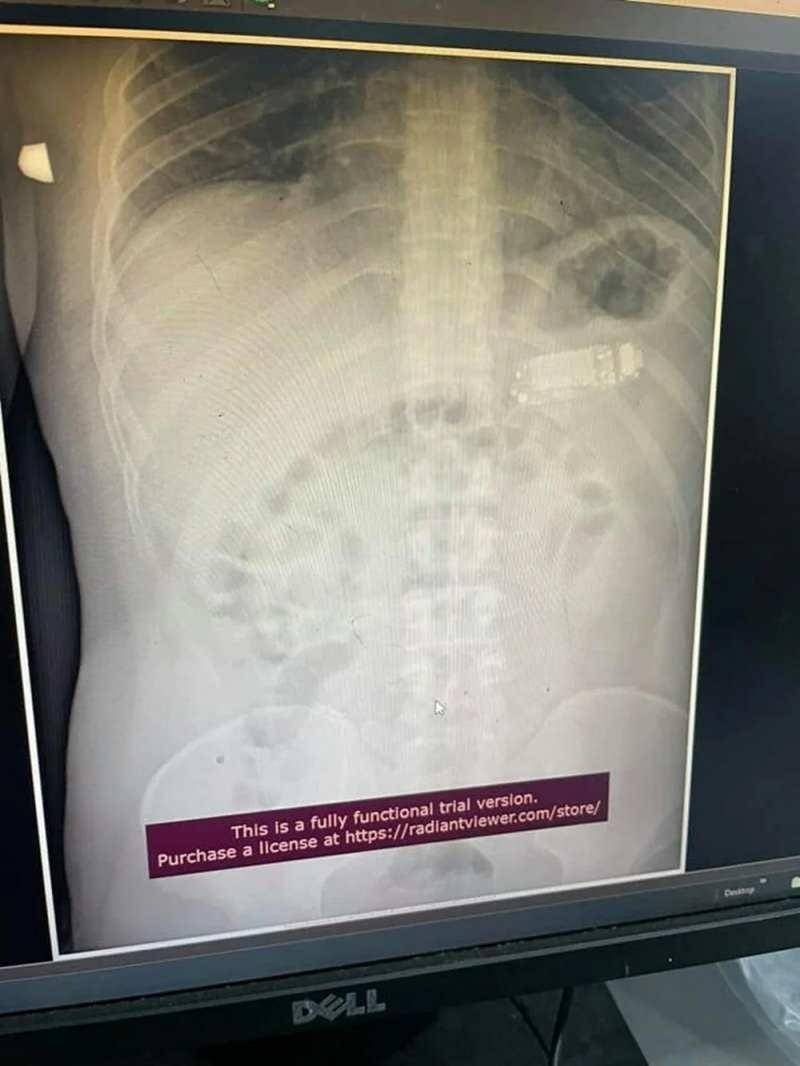

Başarılı operasyonu gerçekleştiren sağlık ekibinin başındaki doktor Skender Teljaku, adamın midesinden çıkarılan telefonun fotoğrafları ile röntgen ve endoskop görüntülerini Facebook'ta yayınladı.

Teljaku yaptığı açıklamada, tıbbi ekibin telefonu mideyi kesmeden, endoskop olarak bilinen özel cihazlar kullanarak üç ayrı parçaya ayırmayı başardığını söyledi. Teljaku, ayrıca yaklaşık iki saat süren işlem sırasında "herhangi bir komplikasyon" yaşanmadığını sözlerine ekledi.